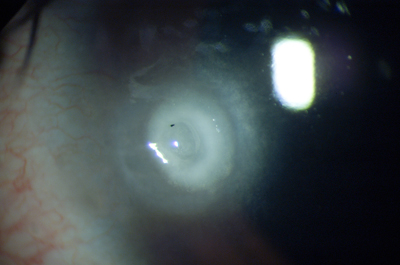

Descompensación de la Córneal Primaria

Distrofia Endotelial de Fuchs, conocida como córnea Guttata por el aspecto de las verrugosidades que aparecen en el endotelio. Con retroiluminación, (reflejo rojo) el aspecto endotelial es el de la plata martillada. Es una entidad familiar hereditaria y progresiva pero que toma décadas para desarrollarse. Produce pérdida de la transparencia de la córnea por incapacidad del Endotelio para mantener el estado de deshidratación corneal.

Los signos y los síntomas de la distrofia se hacen evidentes después de los 50 años con visión borrosa mayor al despertarce que mejora a lo largo del día. A medida que progresa, los periodos de emborronamiento se van haciendo más largos y permanentes.

Descompenzación Corneal

Descompenzación Corneal

Descompensación Endotelial Secundaria

Espontánea o inducida por trauma accidental o quirúrgico, que reducen la población celular en el Endotelio, provocando edema corneal progresivo y pérdida de la transparencia. Es una entidad que cursa con inflamación, es dolorosa y de curso rápido.